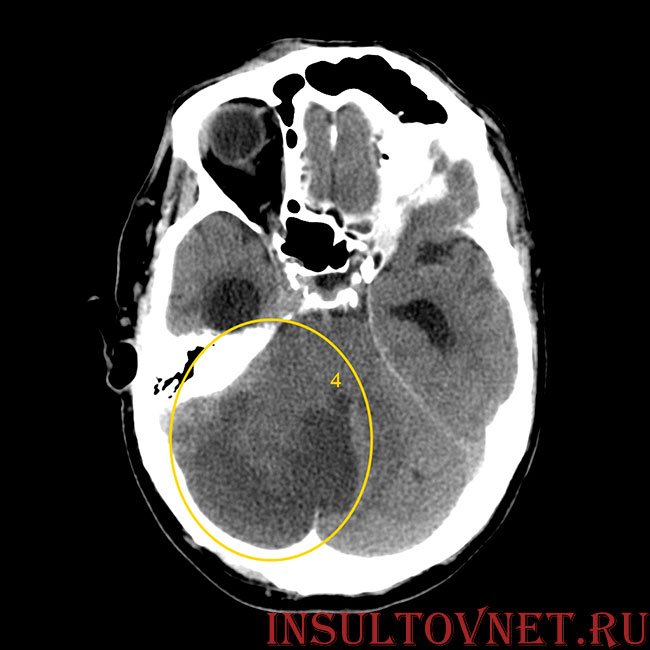

- Нейрохирургические операции по удалению внутримозговых гематом, если имеет место геморрагический инсульт. Разрыв сосуда вызывает истечение крови в ткань головного мозга. Иногда образуются скопления крови – гематомы, которые необходимо опорожнять хирургическим способом. Чем раньше это будет сделано, тем более вероятен благоприятный исход.

- От объема пораженной области головного мозга. Здесь работает простое правило, чем больше инсульт, тем серьезнее его последствия и прогнозы на выздоровление. Обширные катастрофы часто приводят к нарушению сознания, судорогам и коме. Пациенты длительное время находятся без движения. Увеличивается риск инфекционных осложнений, застойных пневмоний, пролежней. Все это отдаляет человека от полноценного выздоровления.

- От локализации тромбированного, если имеет место ишемический инсульт, или кровоточащего сосуда при геморрагическом. Каждая область головного мозга контролирует определенные действия и функции организма. Одна зона отвечает за речь, другая за движения или зрение. Существуют так называемые жизненно важные центры. Среди них области мозга, отвечающие за дыхание, работу сердца. Нарушение кровообращения в этих местах значительно ухудшает дальнейший прогноз.